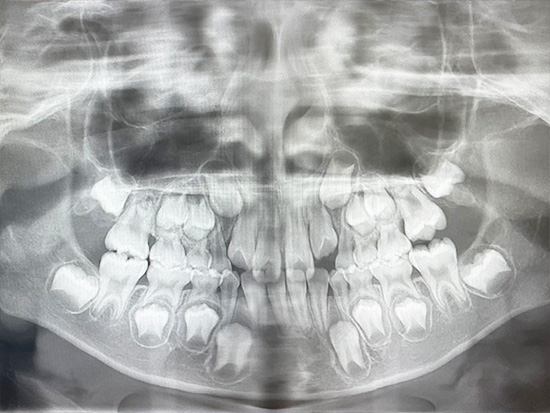

次男の歯のレントゲン写真。歯が大きいそうです。

長男の矯正時に、上顎を広げるのは9歳くらいまでと覚えていたので、念のため8歳の次男も検査してもらうことにしました。検査内容は、資料取り・CT検査・口腔内の菌検査などです。すると、一本一本の歯が標準より二回りほど大きい歯だったようで、今の顎には収まりきらないだろうというお話を聞きました。あまり食べ物を噛まないで丸飲みに近い感じで早食いだったのも、顎の狭さに影響があったようです。